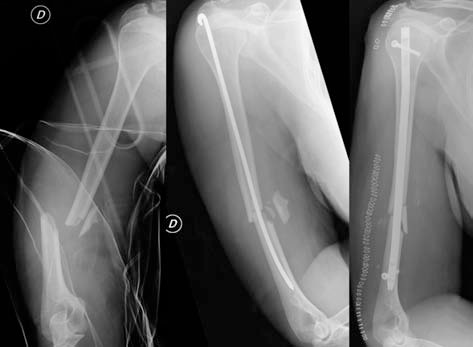

- Fig. 1. Fracture of the middle third of the humerus in the left picture, in the middle picture urgent stabilization with intramedullary Rush nail, in the picture on the right the stabilization with locked intramedullary nail during the simultaneous revisi